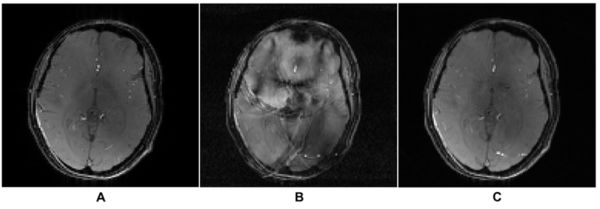

By capturing the combined effects of spatial encoding fields, eddy currents, field nonlinearity and system imperfections, this data-driven approach is highly error-resilient and widely-applicable, especially in scans where advanced oscillating fields are employed to achieve rapid imaging. The effectiveness of the presented auto-calibration technique is demonstrated in Figure 1, which compares reconstructed in-vivo brain scans accelerated by additional oscillating spatial encoding fields, both without and with the application of the invented method.

Figure 1.(A) Reference image without acceleration by additional oscillating spatial encoding fields.

(B) Image reconstructed from 3x3 accelerated scans with additional oscillating spatial encoding fields. The conventional calibration method based on explicit field-mapping scans and current monitoring is used to estimate the additional spin phase evolution imposed by the fast-oscillating spatial encoding fields. Strong artifacts appear in reconstruction due to the calibration errors in the estimated phase evolution maps.

(C) Image reconstructed from 3x3 accelerated scans with additional oscillating spatial encoding fields. The spin phase evolution maps used for reconstruction is obtained by the auto-calibration method as described in this tech offer, which enables artifact-free highly accelerated MRI.